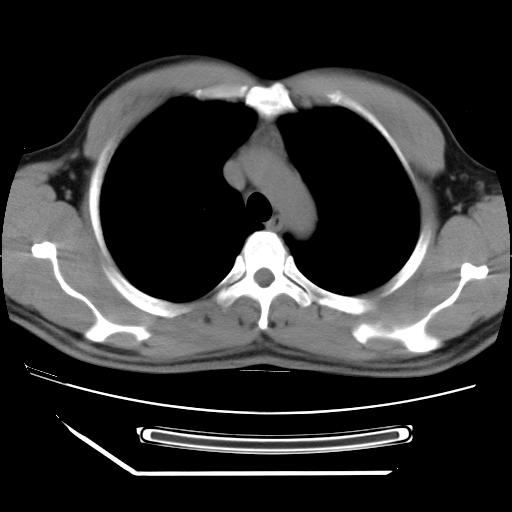

标题: CT21560:胸部肿块影,请会诊

男,38岁,于2009年8月9日晚突发左侧胸痛,今x线提示左下肺阴影,为了明显确诊断,行ct检查,

血常规:嗜酸性细胞增高,单核细胞增高。

纵膈窗

虽然实验室检查支持炎性病变,且病变内有坏死改变(中央呈大片状低密度影),但仍不能掉以轻心,鳞癌也可以有这种影像改变。

病灶发生在下叶,密度均匀,边缘模糊、毛糙,周围血管纹理增强扭曲改变,靠近胸膜处病灶胸膜反应明显。

支持考虑---球形肺炎。